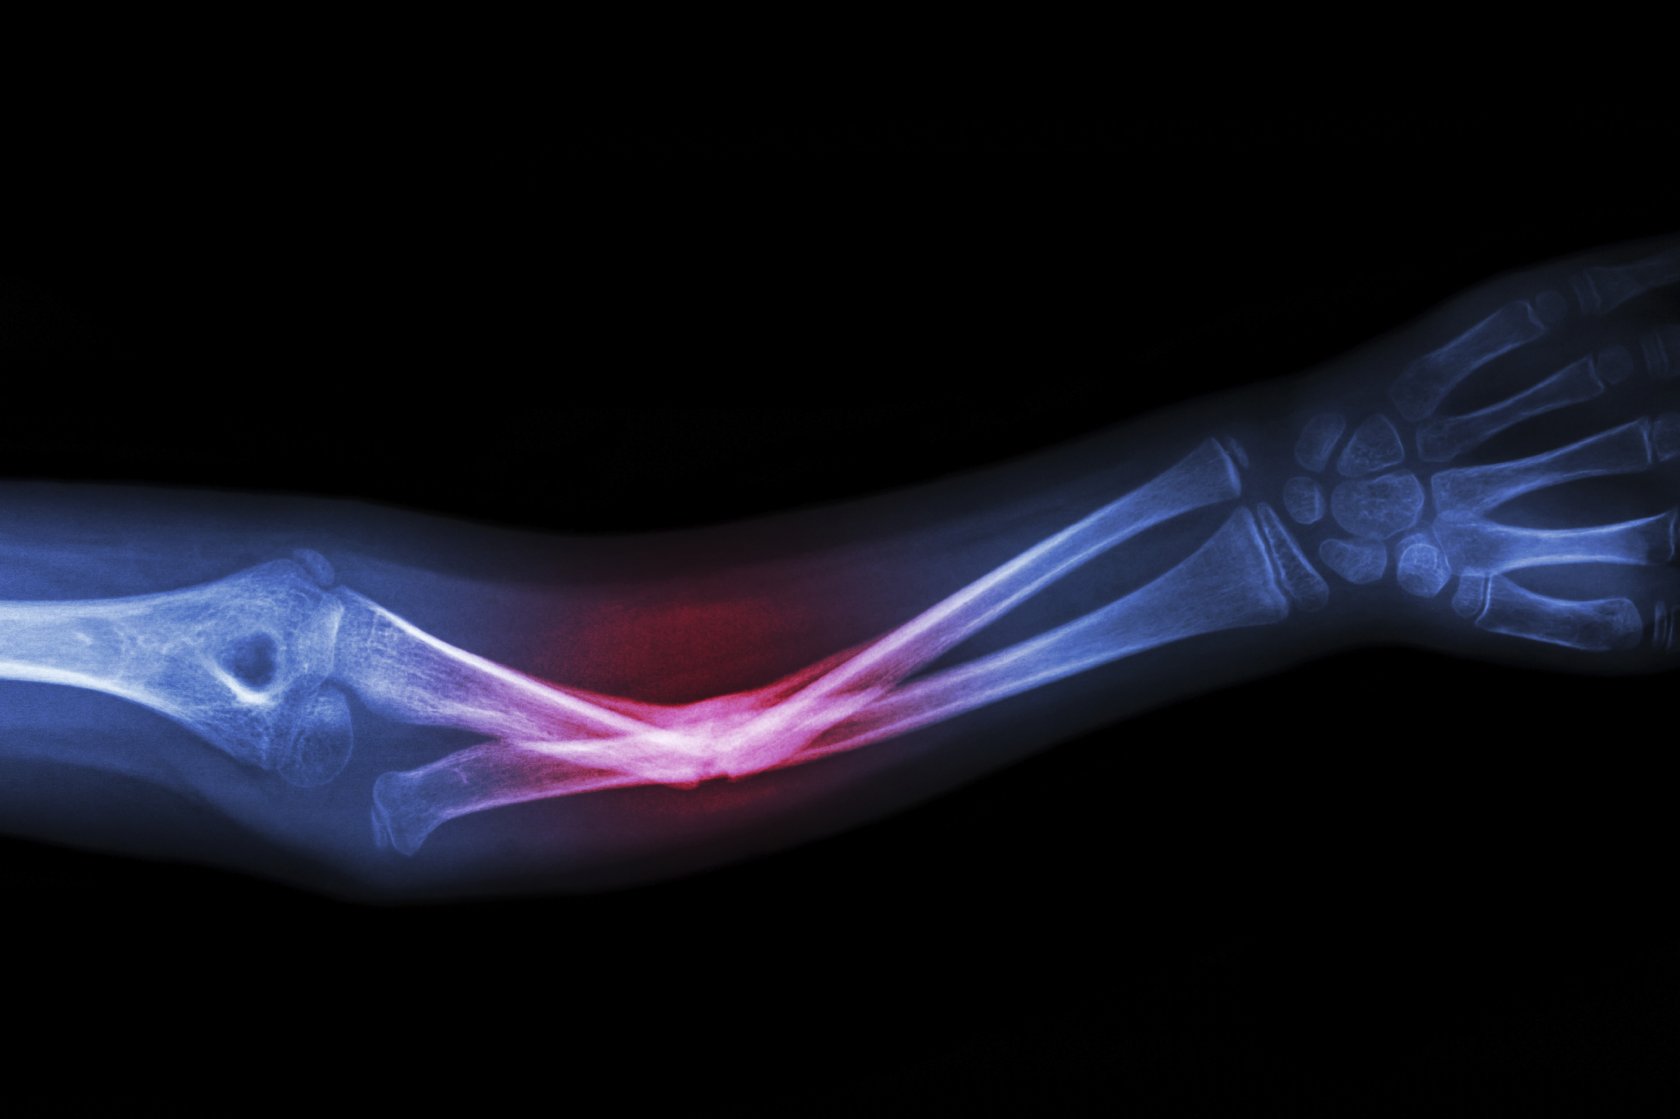

Рентгеновское излучение фото для презентации - 84 фото